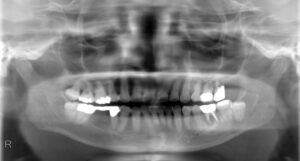

下顎大臼歯2本欠損症例

BEFORE AFTER 48歳男性/下2本/インプラント埋込手術 【治療内容】 左下第一・第二小臼歯の被せ物が外れてし…